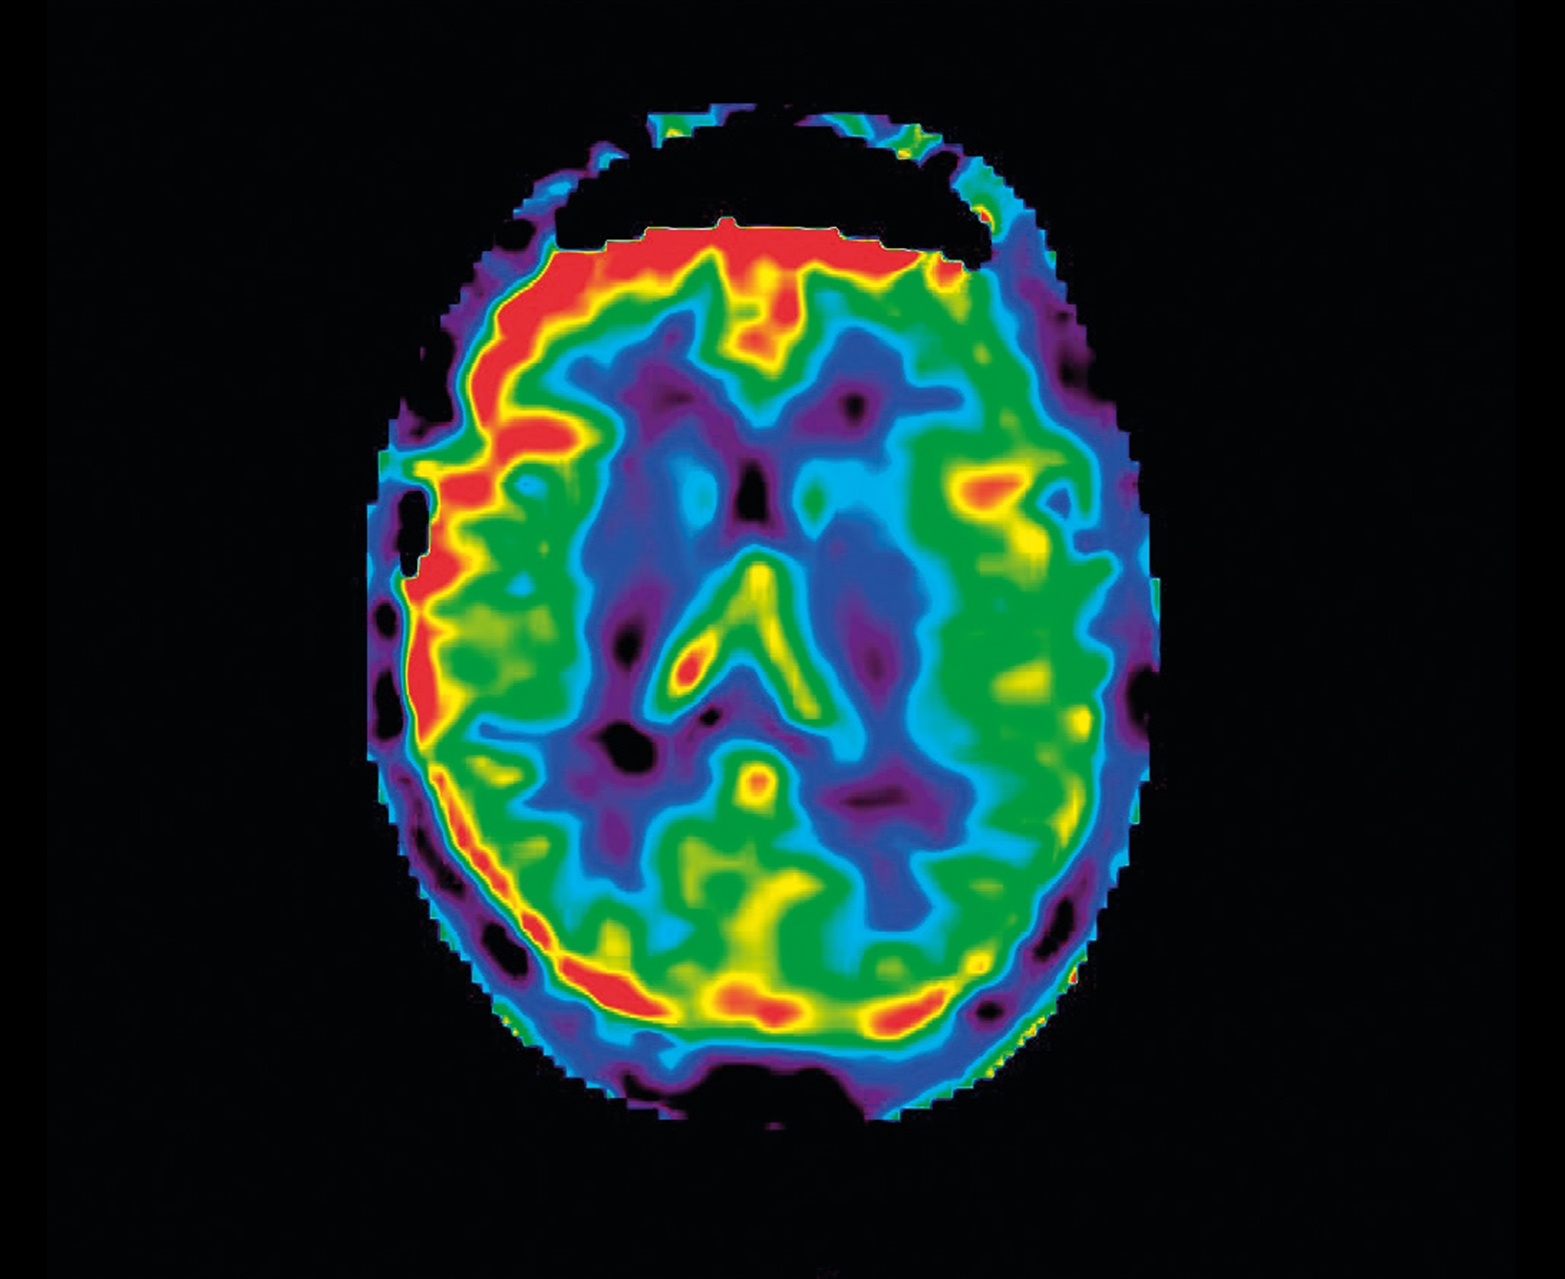

Неконтрастная перфузия ASL